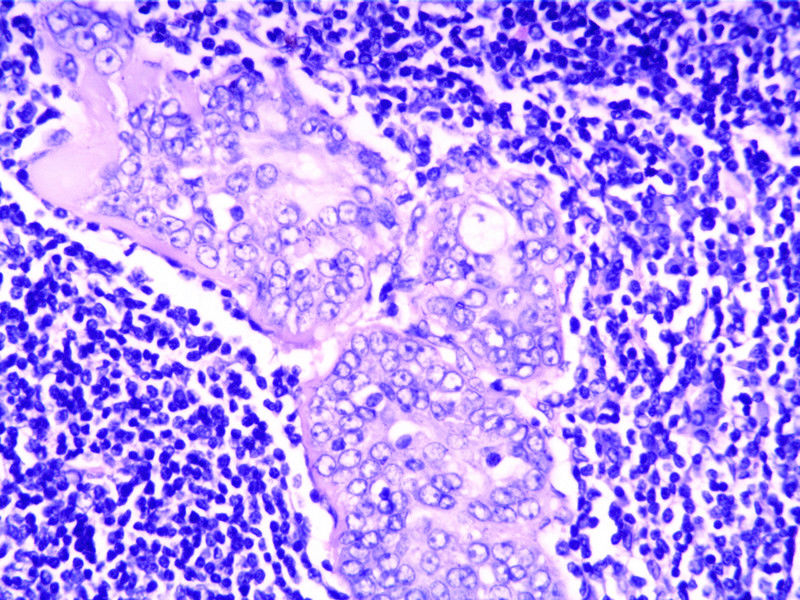

这个肿物有些Hold不住

图1

性别

女

年龄

46

临床诊断

肿物

临床症状

发现肿物3年

标本名称

腮腺

大体所见

肿物V3*2.5*2.5cm,界清。

考虑转移癌。

发现肿物3年多,无手术史及特殊病史。